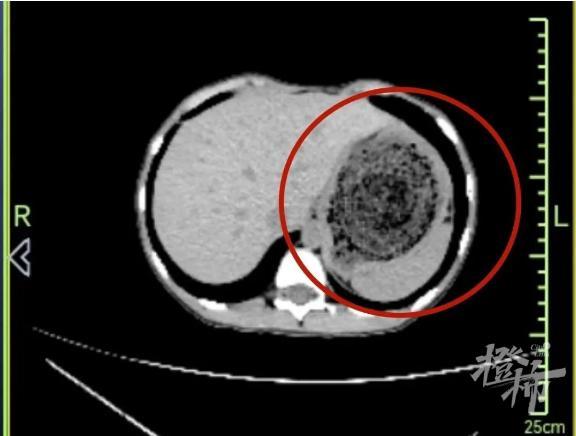

直到最近几个月,小雅上腹痛得越来越厉害,还时不时恶心、干呕,胃口越来越小。小雅看起来比同龄儿童的生长发育明显迟缓,家人带着她到当地儿童医院CT及胃镜检查后,吃惊地发现:她的胃腔已经被密密麻麻的头发填满了。大量的头发跟食物残渣裹在一起,越滚越大,越团越牢,形成了有韧性、无法消化的“胃石”,胃石长期压迫着胃壁,造成了胃多发溃疡及糜烂性胃炎,引起明显胃疼。

即便是有着30余年消化内镜操作经验的季峰主任医师,看到小雅的CT报告,也不由得眉头微皱:经过长年累月的聚集,头发经过胃酸的“加工”和胃的“蠕动”,胃内的毛发结石就像被水泥封印了般,很硬;“石头”横径超过10cm、长径约20cm,充满整个胃腔,小雅的食道入口和胃出口,都比这个“石头”小很多。另外,外院曾多次尝试异物钳取石失败,再拖下去,有可能诱发溃疡穿孔导致腹膜炎,会有生命危险。